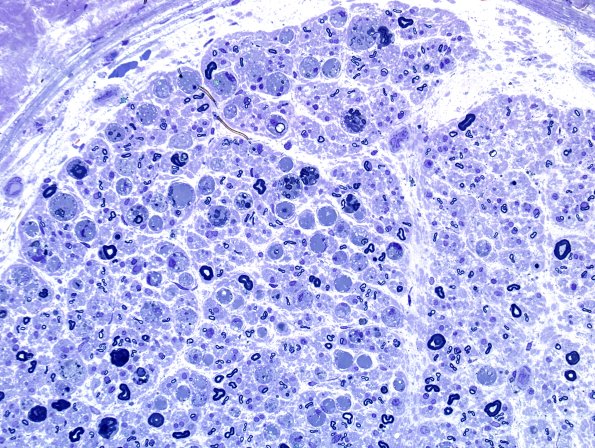

4 AXONAL DEGENERATION

10A2 Axonal Degeneration, fulminant (Case 10) Plastic 4.jpg

This is fulminant axonal degeneration.